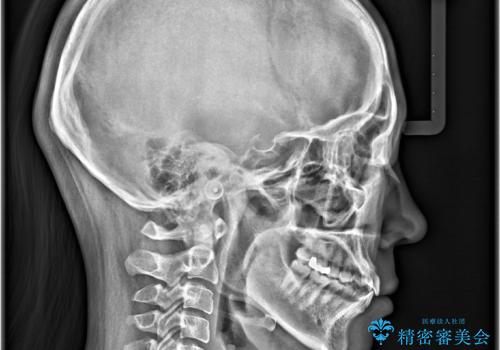

- 歯の捻じれやデコボコを主訴にご来院された患者様です。

矯正治療の精密検査を行った結果、非抜歯(歯を抜かない)矯正治療を選択いたしました。

本症例では、治療の途中で**バイトアップ(咬み合わせを一時的に挙上する処置)**を行い、

上下の歯が干渉しない環境を作りながら、捻転や叢生の改善を進めました。

これにより、歯を無理に動かすことなく、効率的かつ安全に歯列を整えることが可能となります。

その結果、約10ヵ月という比較的短期間で歯列と咬み合わせが整い、機能面・審美面ともに良好な結果を得ることができました。